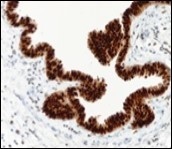

Figure 12.Cutaneous ciliated cyst with nuclear immune reactivity to oestrogen receptors (19).

Epithelium of cutaneous ciliated cyst is immune reactive for pan cytokeratin (CKae1/ae3) antigens, epithelial membrane antigen (EMA), oestrogen receptors (ER), progesterone receptors (PR), Wilm’s tumour protein (WT-1) and paired box gene 8 (PAX8). Immune non reactivity is cogitated for S100, smooth muscle actin (SMA), carcino-embryonic antigen (CEA), desmin, thyroid transcription factor(TTF1), p63 and glial fibrillary acidic protein (GFAP).

Smooth muscle actin (SMA) is immune non reactive, thereby suggesting an absence of smooth muscle within the cyst wall. Intense immune reactivity can be cogitated within epithelial nuclei for oestrogen receptors (ER) and progesterone receptors (PR). Aforesaid immune reactions are indicative of Mullerian origin of cutaneous ciliated cyst.